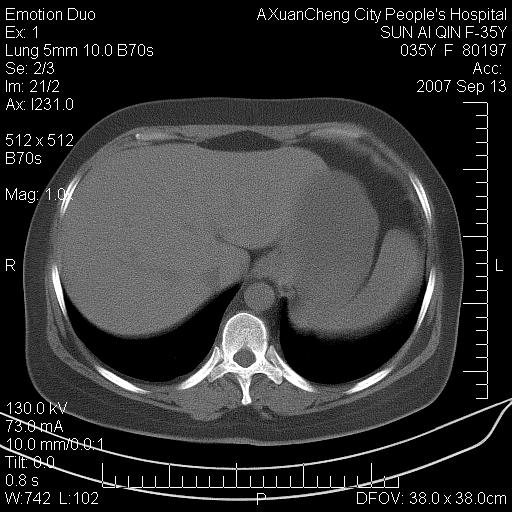

以下是引用ydx_74在2007-9-13 15:42:00的发言:[br]仅看片,考虑右上肺癌并双肺转移,结合病史,考虑肺门、肺内淋巴侵润

以下是引用同在2007-9-13 15:08:00的发言:[br]支持肺门及双肺侵润.